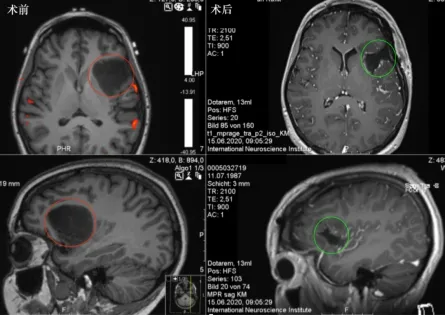

图:巴特朗菲教授手术图片

术前术后影像资料:

图:术前MR显示岛叶占位,直径约为4 cm,紧邻重要脑功能区,包绕左岛叶的大部分,并在背侧延伸至岛叶的后部。术后MR显示肿瘤全切,无脑出血、水肿等正常脑组织损伤。